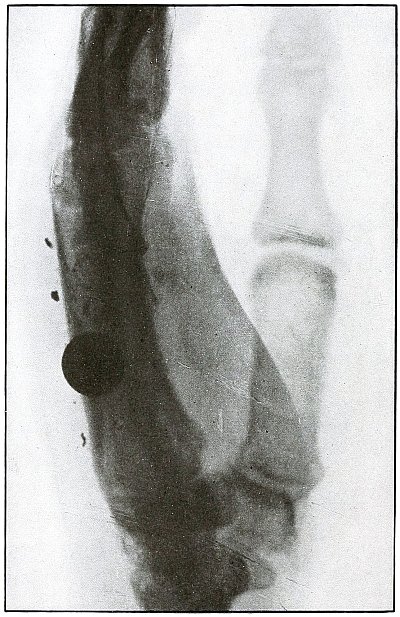

[Pg 94]

Plate 42.

[Pg 95]

Rifle—Plate 42.

UPPER EXTREMITY.

Gunshot Fracture of the Wrist.

This plate, presenting a lateral view of the wound shown in

plate 41, shows considerable deformity of the

joint, after four months’ treatment, which was even more marked two

months later, when the case was discharged with an ankylosis of the

wrist joint, contracture of the flexor tendons of the fingers, and

slight flexor function of the thumb, permitting apposition with the

first finger.

The result, while leaving much to be desired, preserved a function of

the hand vastly superior to that of a forearm stump.

The treatment in such cases is always courageously conservative, with

amputation only as the extreme measure to save life, with risks of

judgment in favor of conservatism.

Corrective measures may be employed after management if the treatment

of the infection is successful and when the case passes out of the

military category. It is not possible, during a long infection, to

maintain better position in such cases.

[Pg 96]